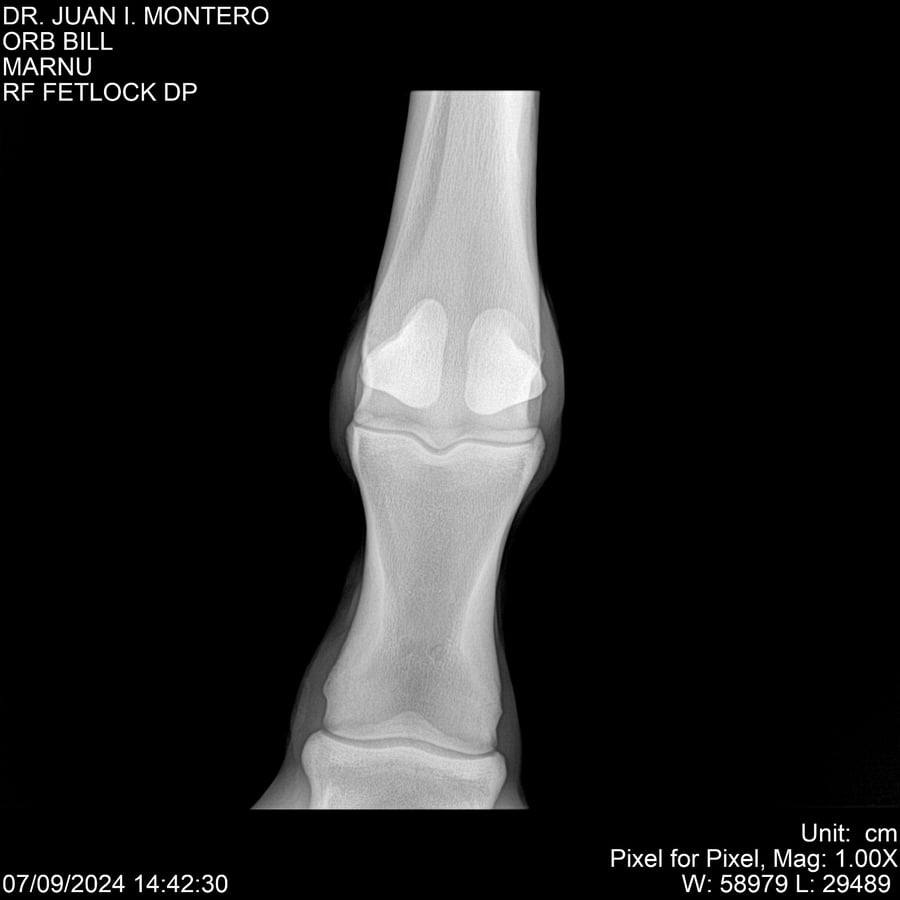

LOTE 7, ORB BILL 🔥 🔥 🔥 Lote Anterior Volver al remate Lote Siguiente Ficha Contacto Montevideo - Ficha del Lote Identificador: #282523 Categoría: Yeguarizos Montevideo - 83 Visualizaciones ClicData Contacto Empresa: Abelenda N. R., Walter Hugo Nombre*: Teléfono* : E-mail* : Mensaje Enviar Registrese gratis Este contenido Exclusivo está disponible sólo para usuarios registrados Ingresar